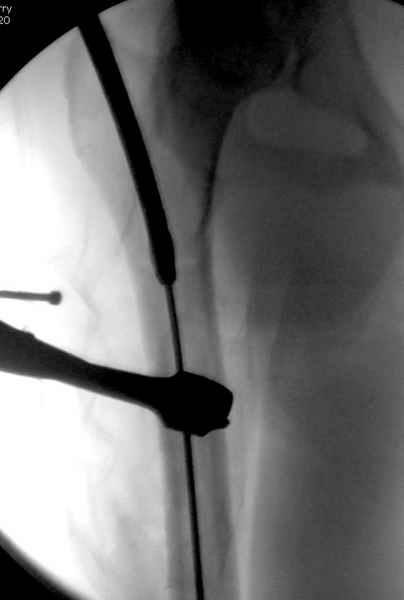

Как раз недавно у меня был примерный случай: больному 36 лет, поступил ночью, травма в результате мотоциклетной аварии, кроме чрезвертельного и спирального перелома левого бедра имеется переломы костей предплечья с этой же стороны. Скелетное вытяжение, а на следующий день больной про оперирован на ортопедическом столе с дистракцией. Чтобы не расколоть чрезвертельный перелом провели временную спицу ближе к переднему кортексу, из малого разреза костодержатель для репозиции, а фиксацию провели антиградным штифтом. Этапы операции на снимках.

Джолдас Кульджанов